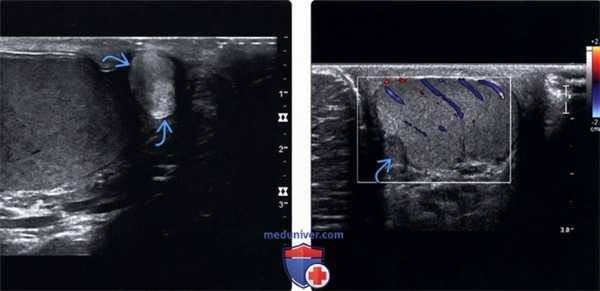

3. УЗИ при аденоматозной опухоли мошонки:

• Солидное объемное образование внутри придатка яичка или белочной оболочки вариабельной эхогенности:

о При легком надавливании датчика можно наблюдать, что объемное образование двигается независимо от яичка

• При В-режиме УЗИ определяется рефракционная краевая акустическая тень

• Гиповаскулярное или аваскулярное по данным цветовой допплерографии